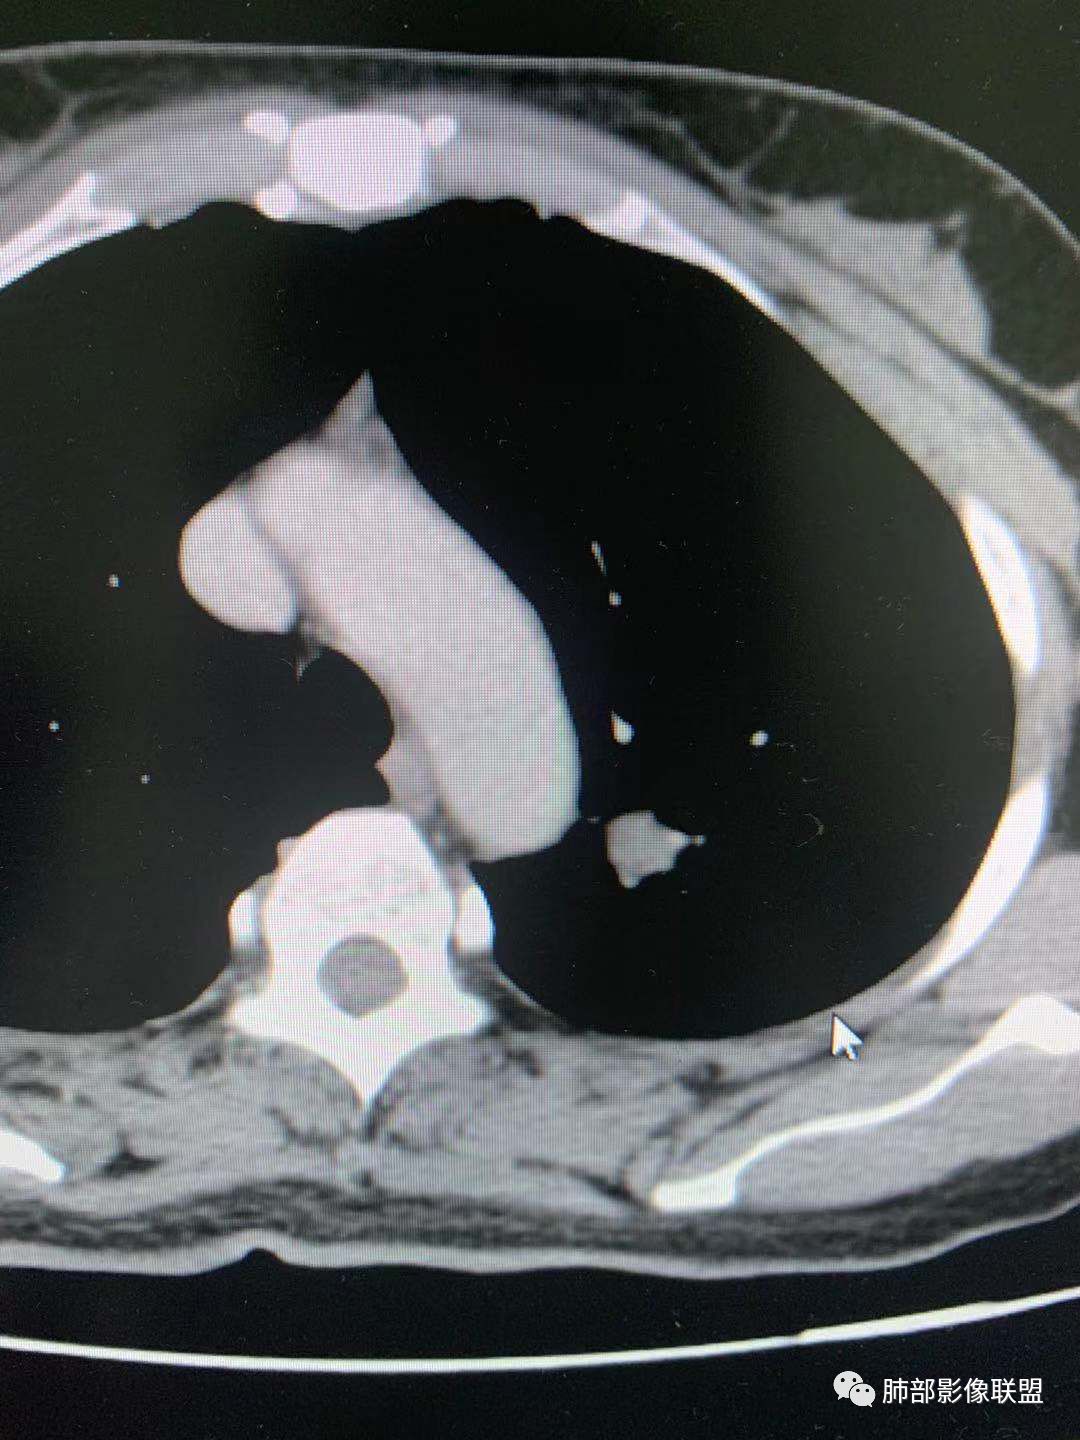

一.尖后段高密度大结节:

1.左肺上叶尖后段较大类圆形实性密度结节影,密度均匀,中等程度强化。

2.实性密度区边缘相当清楚,表面欠光整,偶见毛刺、棘突和旁出血管结构,未见典型的深分叶及邻近胸膜凹陷。

3.可疑支气管进入受阻。可惜缺乏连贯图像或冠矢状位以资判断。

4.病灶与胸膜之间有连线,邻近段支气管及肺血管整体后移,提示病灶还是有一定收缩性。

如上,单就这实性结节,硬化性肺细胞瘤(PSP)和腺癌似乎都能够解释,形态太规整了一些。

5.病灶周围见边界清楚的磨玻璃影,有点醒目,有点意外!

这是无论如何不能忽视的征象!

这点强烈提示,要么整个病灶恶性(腺癌),要么良性病灶旁滋生恶性病灶。

两年前左上肺的病灶什么位置,什么模样,是否相关?我们不得而知。